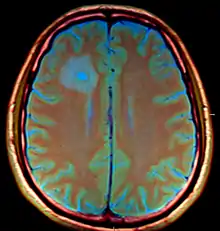

| Brain abscess in a person with a CSF shunt. The abscess is the darker gray region in the lower left of the image (corresponding to the right parietal lobe). The lateral ventricles are visible in black in the center of the brain, adjacent to the abscess.[1] | |